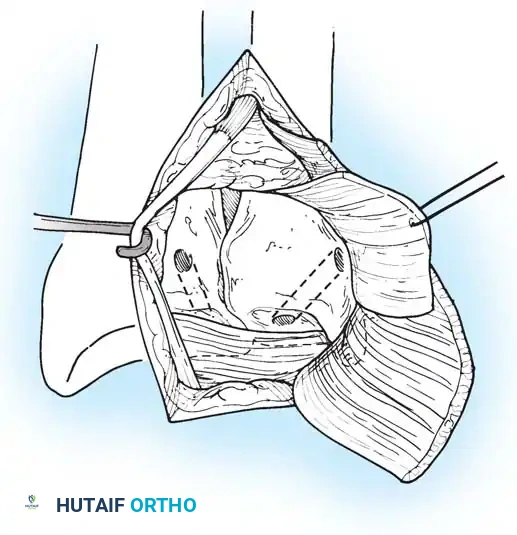

Chronic Instability and TFCC Reconstruction

In chronic settings where the TFCC is irreparable, anatomic ligament reconstruction using a tendon autograft (e.g., palmaris longus) is indicated. The graft is routed through the distal radius and ulnar fovea to recreate the dorsal and volar radioulnar ligaments.

Tendon graft routing through osseous tunnels in the radius and ulna for anatomic reconstruction of the DRUJ ligaments.